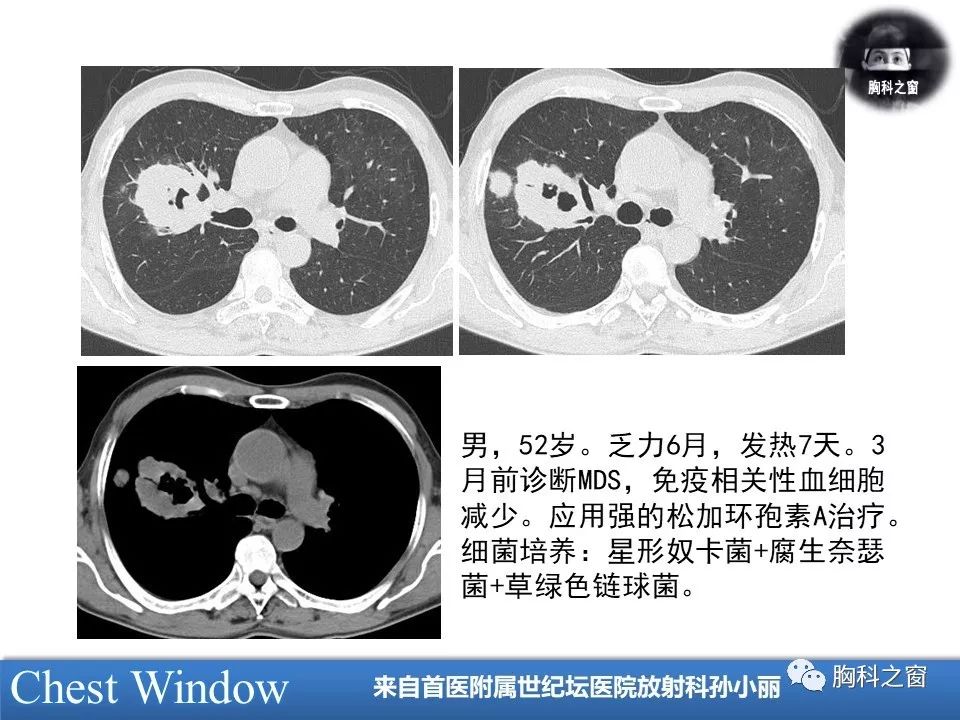

奴卡菌肺炎——张嵩

图片尺寸621x420